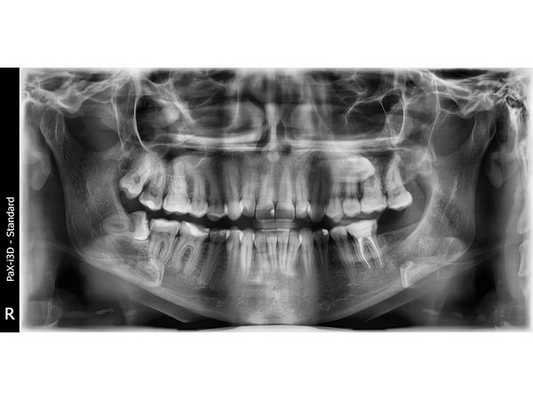

По результатам ортопантомограммы диагностирован медиальный наклон 48 зуба: зуб наклонен вперёд, его передние бугорки упираются в шейку соседнего нижнего зуба справа.

Зуб необходимо было удалить. Пациентке сделали проводниковую анестезию раствором убистезина ДС 1,7*2, выполнили разрез по вершине гребня от 48 до 46 зуба, лоскут отслоили. Корни 48 зуба были сегментированы (разделены на фрагменты путём отпиливания фрагмента коронки зуба) и удалены с помощью прямых элеваторов. Выполнен кюретаж (вычищение) раны, иссечение рубцовой ткани, антисептическая обработка 0,05 % раствором хлоргексидина. Рана заполнена губкой, пропитанной препаратом "Альвостаз". Выполнена мобилизация полнослойных лоскутов, герметичное ушивание раны с использованием нерезорбируемого (невпитывающегося) шовного материала монофил, повторная медикаментозная обработка 0,05 % раствором хлоргексидина. Оперативное вмешательство длилось 25 минут.